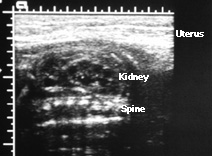

Prenatal Ultrasound of Multicystic Kidney Note the black areas (cysts) that do no communicate.

There is no renal parenchyma. This is a typical ultrasound

appearance of a multi-cystic kidney. Multicystic kidneys

almost always occur unilaterally. What would happen to this

child if both kidneys were multi-cystic kidneys? |